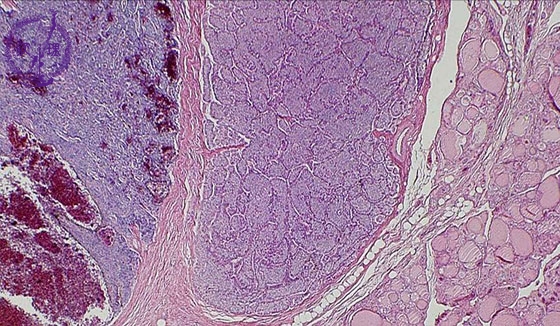

- 13.Endocrine

- (2)secondary hyperparathyroidism

Microscopic findings (HE stain, low power view). Secondary parathyroid hyperplasia. The parathyroid gland was is enlarged with decreased adipose tissue components. Cystic change and hemorrhage were are also detected in the photomicrograph.

Click the image to see the enlarged image.